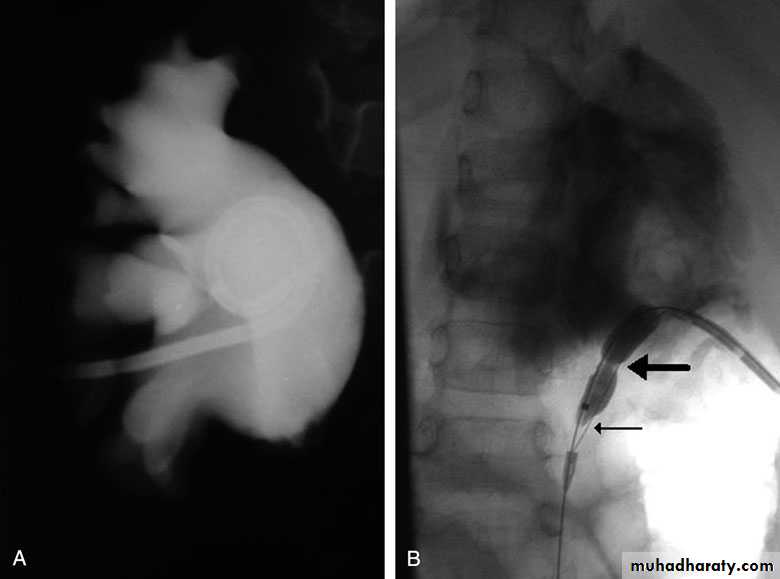

Postcaval (Retrocaval) ureter (Preureteral Vena Cava )

Congenital  anomalies of the upper urinary tract

The right ureter pass behind the inferior vena cava

This might causes obstruction

Diagnosis: IVU

Treatment:

surgical correction involves ureteral division, with relocation and ureteroureteral or ureteropelvic reanastomosis,

usually with excision or bypass of the retrocaval segment, which can

be aperistaltic